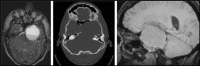

Middle cranial fossa cystic schwannoma

The authors present the unusual case of a 37-year-old man, with a history of hepatitis C, presenting with a 3 year history of progressive trigeminal, facial and vestibular nerve defects. Intracranial imaging demonstrated a cystic middle and posterior fossa lesion, that was ultimately diagnosed as a cystic trigeminal schwannoma. Due to the uncertainties of diagnosis he was managed in two stages with an open biopsy and then a subsequent partial resection. Surveillance of the tumour remnant is planned. The rare nature of this diagnosis is discussed, along with the more common findings in intracranial schwannoma, and the wide differential to be considered. Briefly, the authors describe the surgical option for a complex multi-fossa schwannoma and the importance of the multi-disciplinary team in the diagnosis and management of such patients.